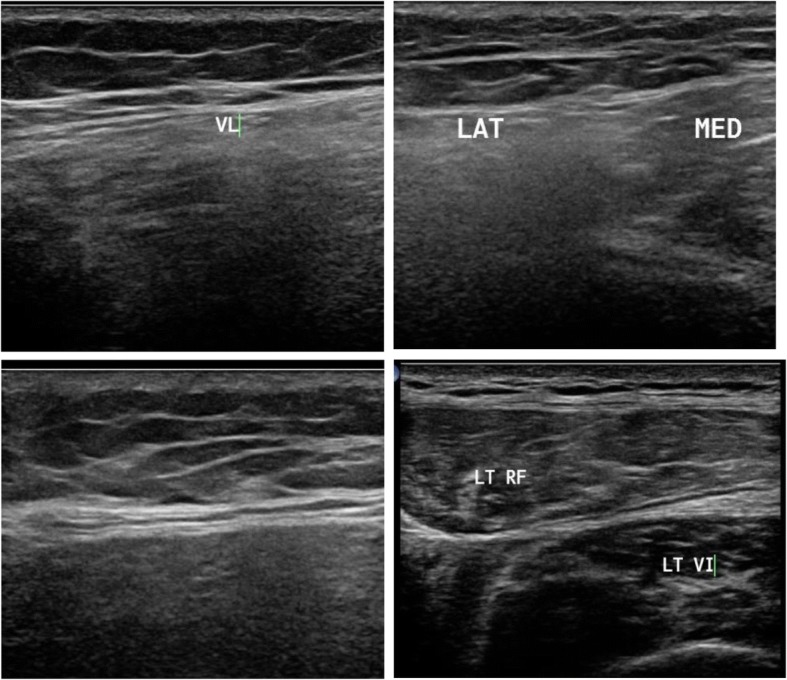

Fig. 3.

Muscle ultrasound in patient with X-linked recessive Emery-Dreifuss muscular dystrophy (EDMD) showing minimal affection in the thigh especially of the vastus lateralis (VL) and vastus intermedius (VI) and in leg selective affection of soleus